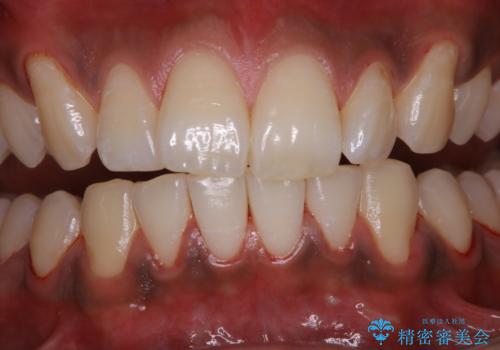

歯についたタバコのヤニをPMTCで綺麗に

- 電子タバコを吸う習慣があり、ステインがついてしまっている見た目が気になるとのことで来院されました。ステインだけではなく、歯石も全体的に付着していたためPMTC60分コースを行いました。